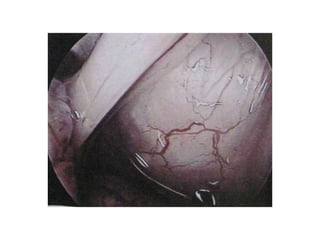

FIGURE 2. In this cystic craniopharyngioma (Patient 5), the stalk was centrally

infiltrated close to the pituitary and could not be preserved A. The incipient third

ventricle entrance is seen from intracavitary view. The slit into the third ventricle is

still covered with tumour capsule B. Complete removal of the capsule opened the

third ventricle C. Petehiae in the hypothalamus bilaterally resulted from apparently

gentle traction and blunt dissection of the capsule away from the hypothalamus

D. Psychoorganic change, disorientation and memory deficits were noticed in less

than a week after surgery, the transient sleep disorder become apparent in the

second week postoperatively (see also a supplemented video material 2).